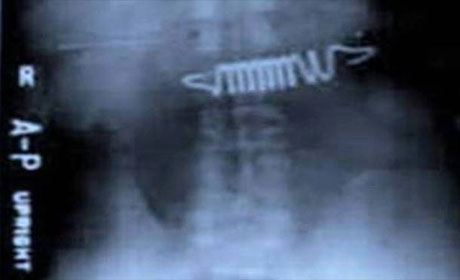

İnsan nələri udmağa qadir deyil? Yaxud mədədən nələr gəlib-keçmir? ANN.Az-in oxuculara təqdim etdiyi fotolar bir daha insanın nələrə qadir olduğunu göstərir. 1. İlan balığı2. Qaşıq3. Batareyalar4. Canlı qurbağa5. Mismar6. Dərmanlar 7. Nişan üzüyü8. Qayçı9. Tük yumağı10. Mobil telefom11. Qələm12. Yay13. Əl bombası14. Açar15. Lampa